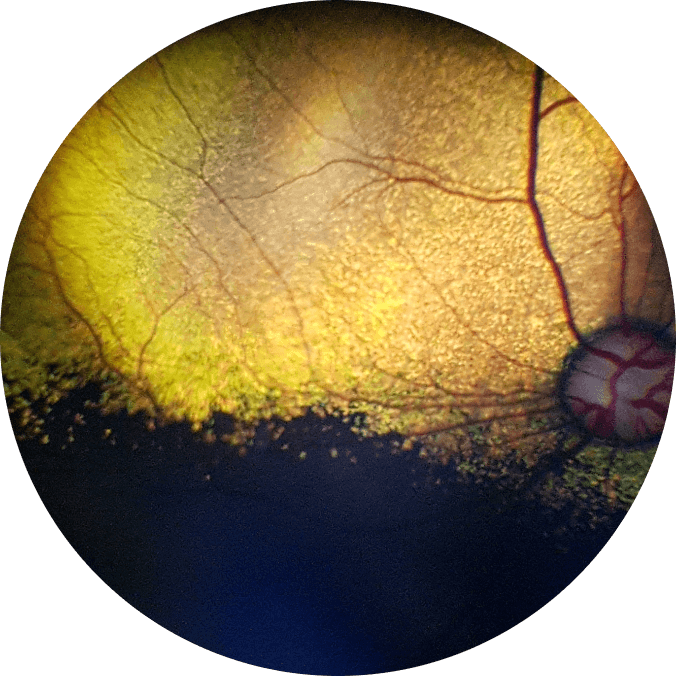

British Shorthair

dilated, 3y, OD